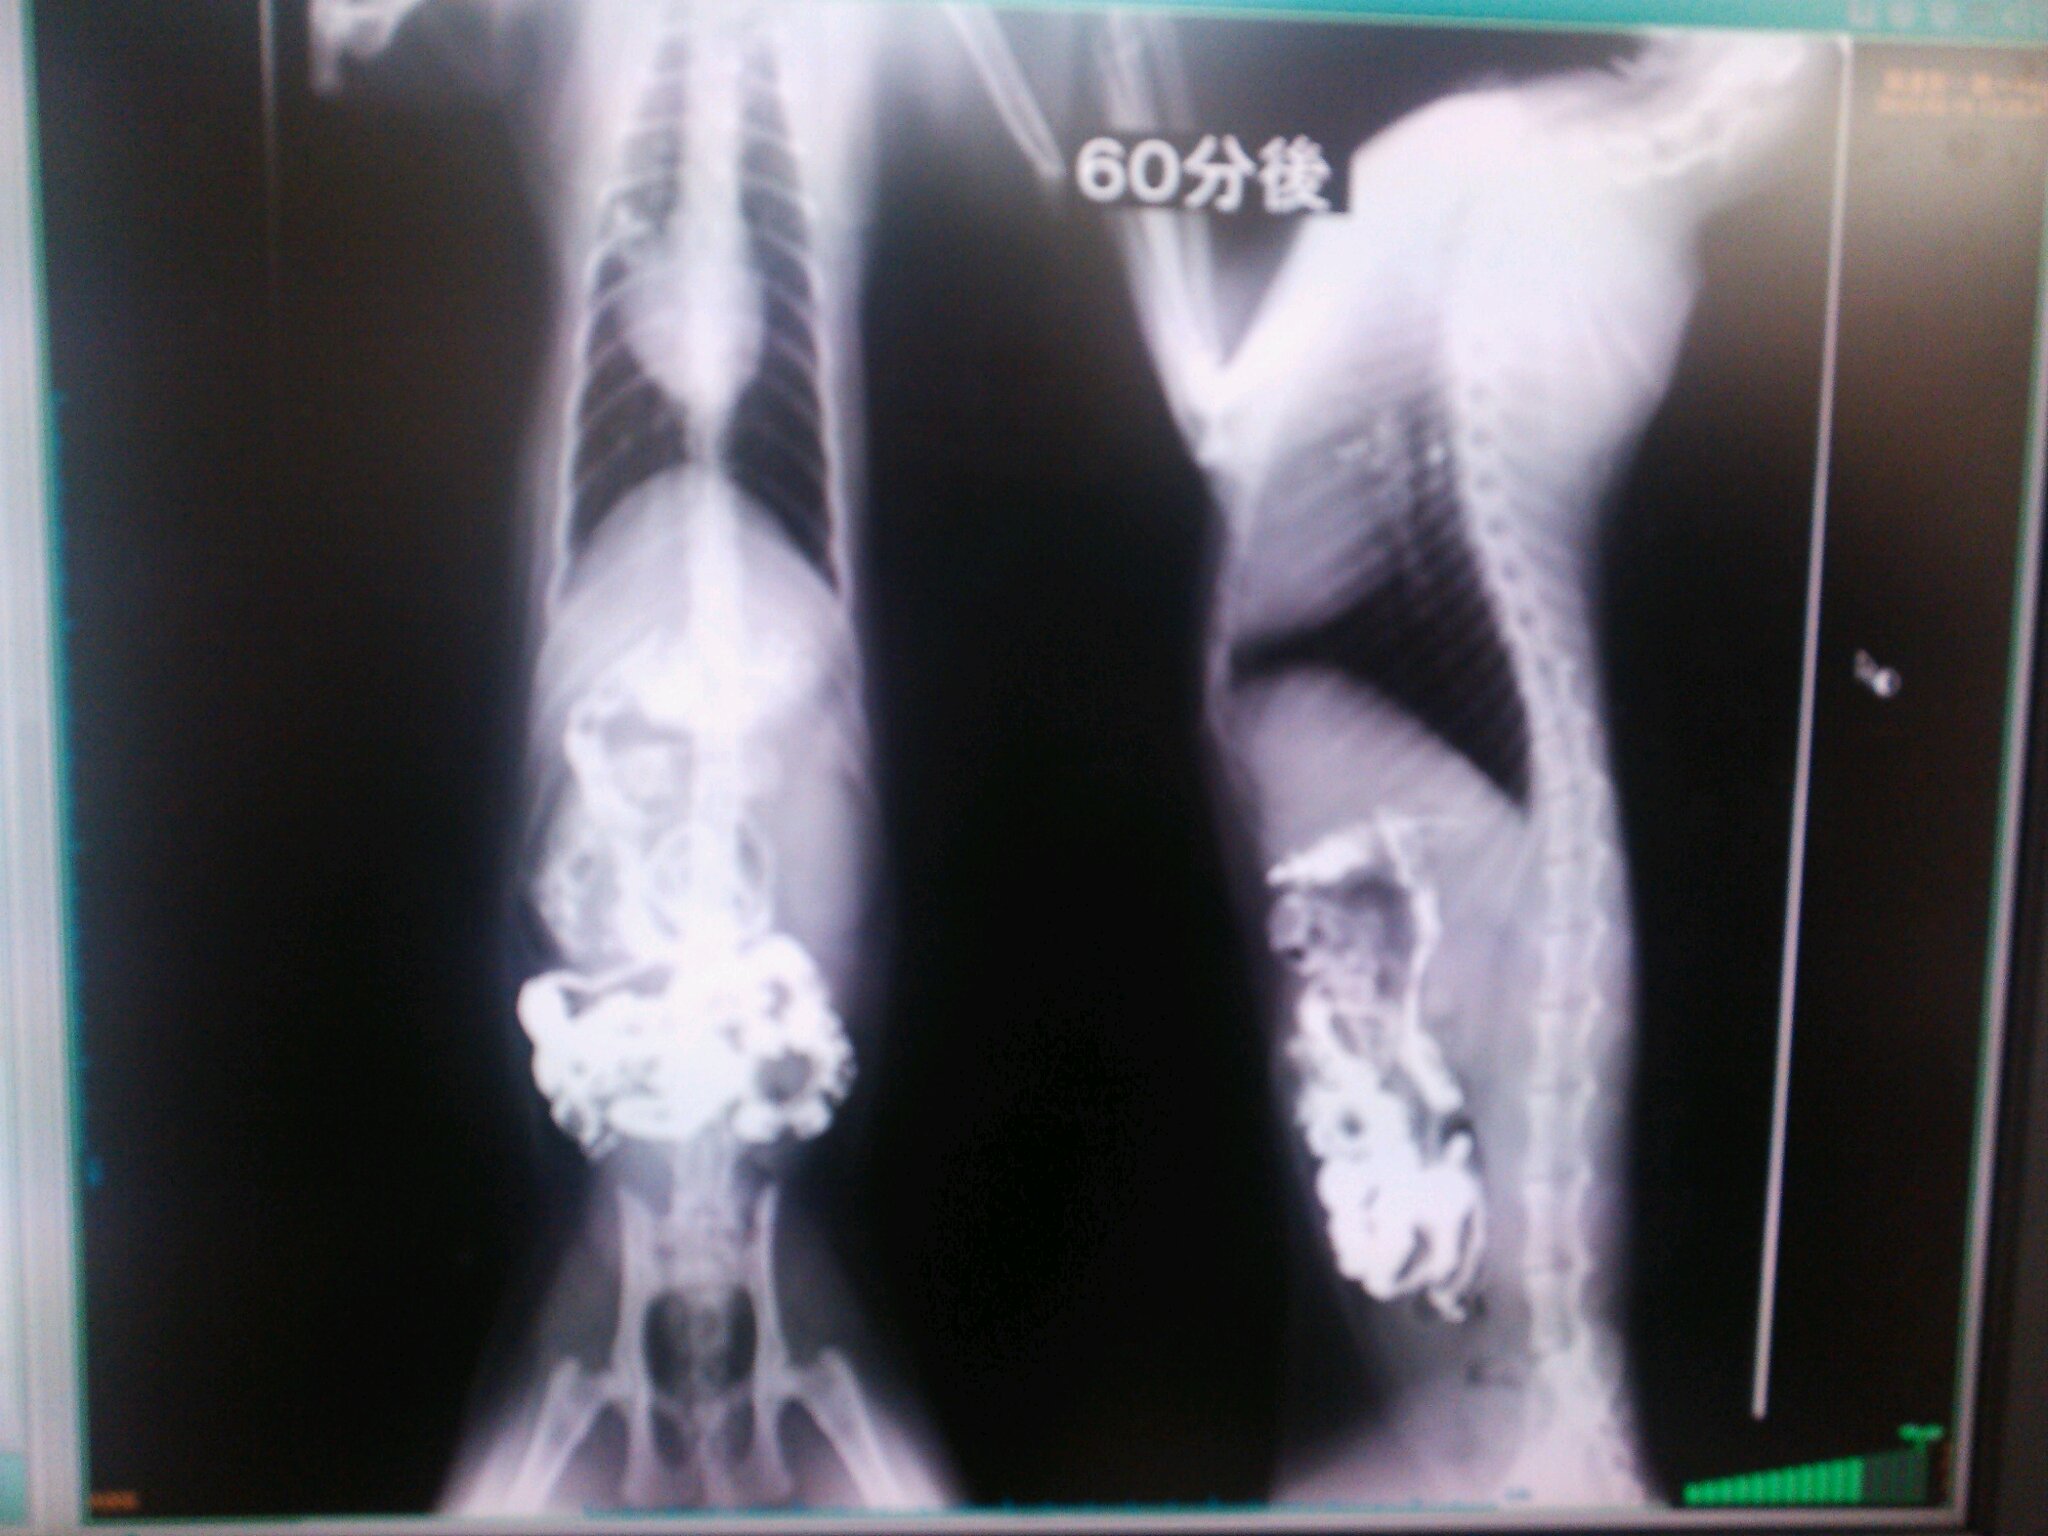

こんなカンジでバリウムが流れていって

どっかで止まれば、そこが腸閉塞っつー話でやんすた。

こんなことを5時間以上続けたらしい。